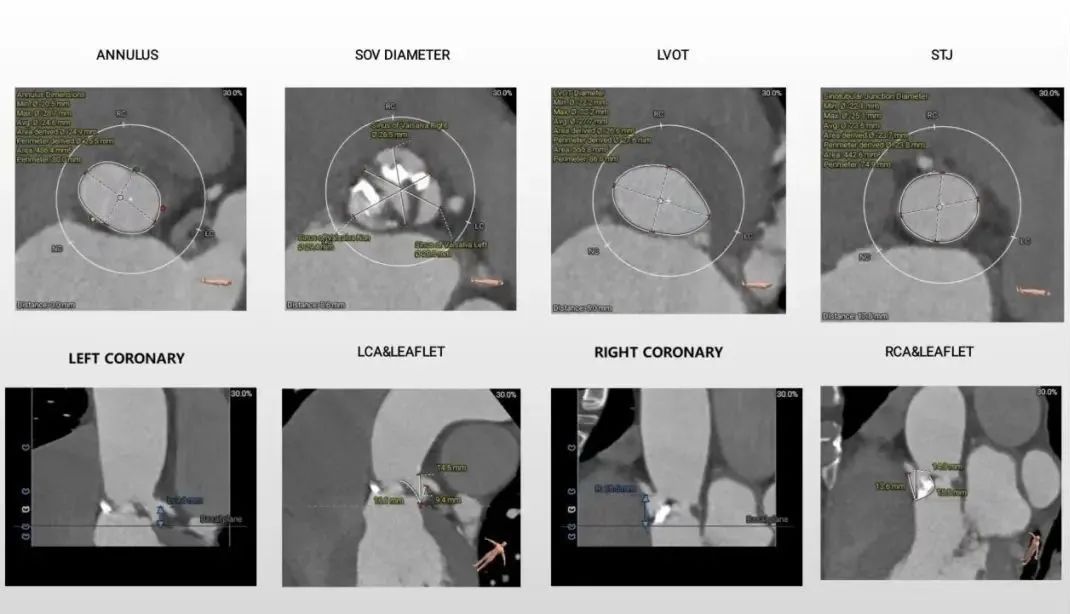

术前评估:

1.主动脉瓣瓣环周长80,平均周长径25.5;

2.Type1型二叶式主动脉瓣,R-L纤维融合嵴,瓣叶增厚,重度钙化,钙化分布不均匀,钙化呈团块样分布在无窦窦底及左冠瓣叶处,左室流出道开口呈敞口状;

3.左冠及STJ开口较低,瓣叶冗长,左、右冠瓣叶长度>冠脉顶端开口到瓣叶附着距离;

4.瓦式窦内径、窦管交界内径偏小,升主动脉内径尚可;

5.主动脉瓣环与水平夹角为50°,非横位心,主动脉弓距及弓部夹角尚可,主动脉弓存在散在钙化;

6.双侧股髂动走行轻度扭曲、左侧股动脉开叉较高,右侧髂总动脉及左侧股动脉内径细。

主动脉根部评估:

瓣环上解剖结构评估: